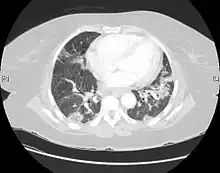

| CT scan of a patient with UIP. There is interstitial thickening, architectural distortion, honeycombing and bronchiectasis. | |

UIP may be diagnosed by a radiologist using computed tomography (CT) scan of the chest, or by a pathologist using tissue obtained by a lung biopsy.

Radiology

Radiologically, the main feature required for a confident diagnosis of UIP is honeycomb change in the periphery and the lower portions (bases) of the lungs.[3]

On high-resolution computed tomography (HRCT), the following categories, depending on imaging findings, have been recommended by a collaborative effort by the American Thoracic Society, European Respiratory Society, Japanese Respiratory Society, and the Latin American Thoracic Society:[4]